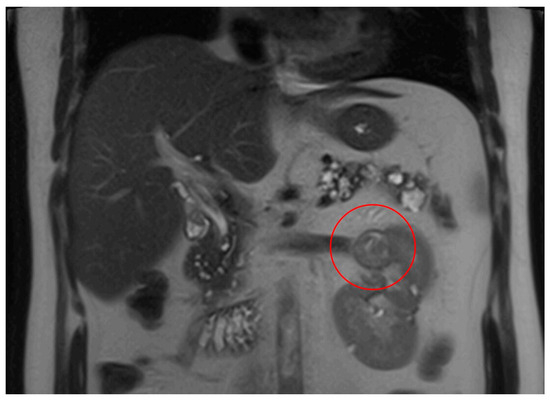

MRI abdomen scan, 21 November 2023, before commencement of treatment with belzutifan: multiple RCC left kidney (largest finding marked).

Figure 4.